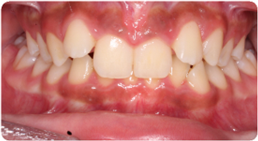

Drag the slider to compare the before and after. This patient presented with severe crowding and overlapping teeth, resolved entirely through BioLign Method-guided aligner treatment.

Each case shows the front view and an arch or side view, before and after BioLign Method-guided treatment.

All cases treated within 6–12 months.

Overlapping teeth resolved through arch form restoration